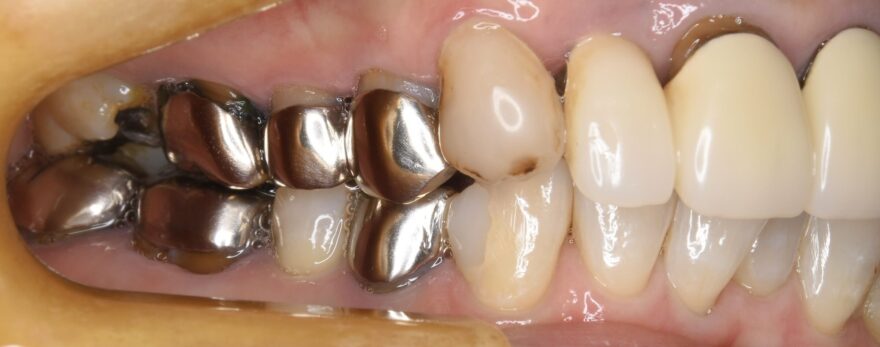

こちらにも、何でも噛める機能的なセラミック歯が入りました。。

こちらも、どこにインプラントが入っているか分からない自然な形態を再現できました。

当院のプレミアムセラミックは、天然歯同様の精密形態再現・多点咬合設計・力の分散コントロールにより、顎関節や筋肉とも調和します。

奥歯の精緻な噛み合わせが、結果として、前歯のインプラントの長期安定につながります。